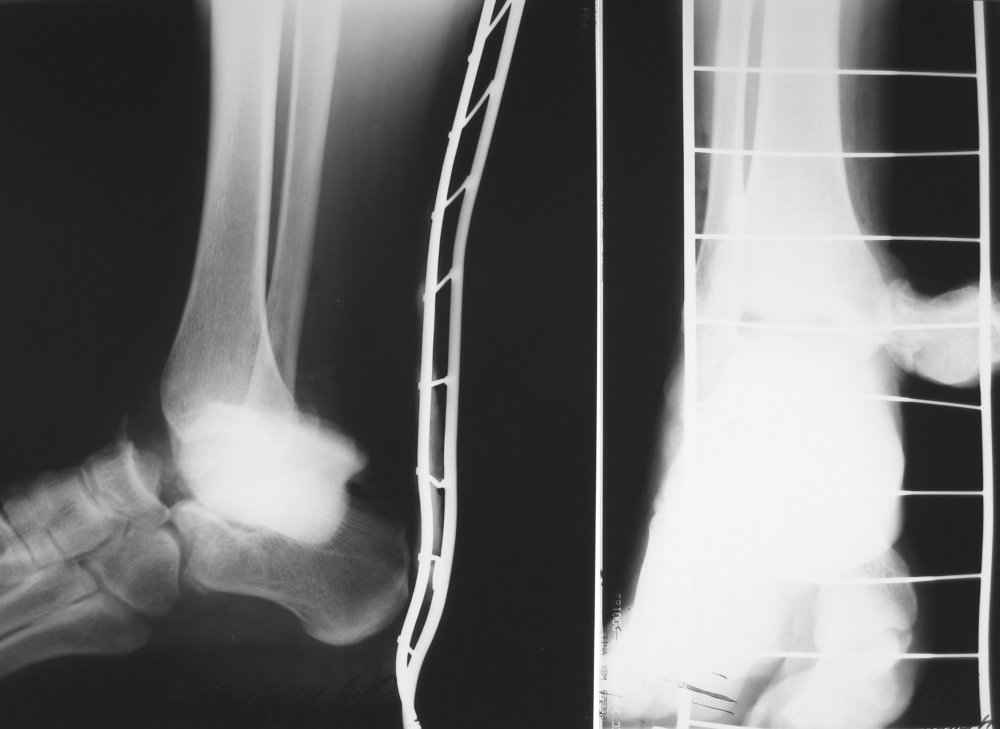

На лечении находится пациент 35 лет. Травма в сентябре 2008 г.- открытый вывих таранной кости

В день травмы ПХО, вправление вывиха, трансартикулярная фиксация. Рана зажила первично. С января нагрузка на конечность. С конца апреля- болевой синдром. На рентгенограммах и КТ признаки ас. некроза таранной кости, артроз подтаранного и голеностопного суставов.